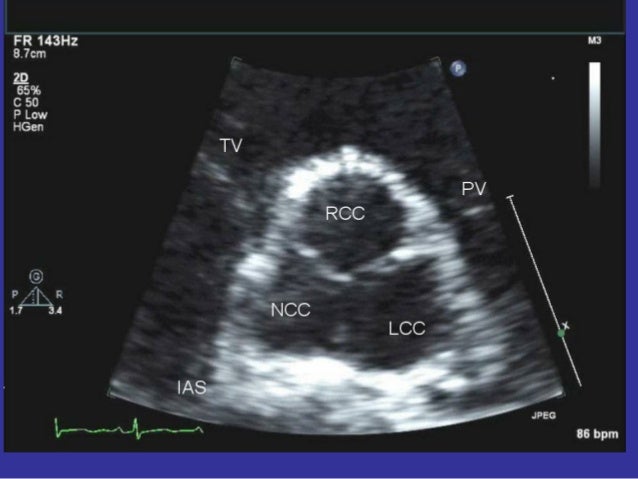

6, 7 In the last decade, a few reports were published on focal AT originating from the non-coronary cusp (NCC). For the echocardiographer looking down at the aortic valve in the short axis view, the non-coronary cusp will be in the 7 o’clock position, the right coronary cusp will be in the 11 o’clock position and the left coronary cusp will be in the 3 o’clock position. Therefore, the patient underwent aortic valve replacement.

Echocardiography, Ultrasound, and Perioperative Medicine Moving our Specialties Forward Normal TTE Quiz. Right Coronary Cusp (RCC) Left Coronary Cusp (LCC) Non-Coronary Cusp (NCC) Therefore, we can associate the RCC with the right coronary artery and the LCC with the left coronary artery. 🔴AORTIC STENOSIS 🔴 🔵 INTRODUCTION * The normal aortic valve consists of 3 symmetric cusps ️ Right Coronary Cusp (RCC), Left Coronary cusp (LCC) & Non- Coronary Cusp (NCC).

Non coronary cusp To receive notifications about the YouTube videos and playlists from echocardiography, click the Subscribe button to. They may be called the left coronary, right coronary and non-coronary cusp. Doppler Echocardiography Color Doppler.

The VSD shunt was restricted by the prolapsed cusp. In the long axis, the ascending aorta should be viewed from the valve to the right. The right coronary cusp, the left coronary cusp, and the non-coronary cusp.

The left aortic cusp gives rise to the left coronary artery, the right aortic cusp gives rise to the right coronary artery and the non-coronary cusp does not give rise to an artery. The mitral valve is also called the bicuspid valve and the left atrioventricular valve. The bottom, left video shows the direct visualization of the aortic valve, as viewed from the aorta, throughout the cardiac cycle.